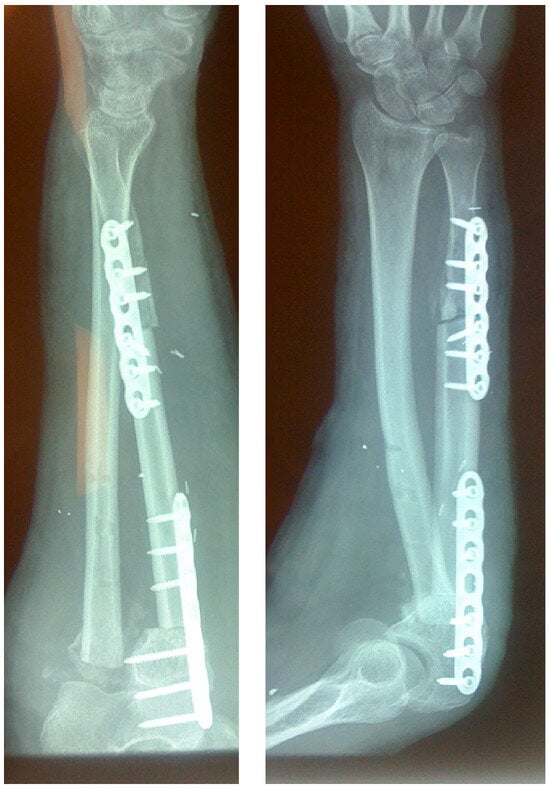

In cases of bone fracture non-union, the surgeon excised scar tissue along with the sequestrum until reaching bleeding bone, following the removal of previously inserted metalwork. For tumor excision cases, the surgeon resected the bone tumor with clear margins or the entire compartment in cases of tumor-induced bone cortex breakage (Figure 1). At this stage, the length of the bone defect was measured to determine the appropriate length of the fibular graft to be harvested (Figure 2). The fibular graft fixation was accomplished using dynamic compression plates (DCPs) or anatomical plates, with a minimum of six cortices engaged on each side using either simple or locking screws (Figure 3). Once the osteosynthesis is completed, it is time to proceed with the vessel anastomosis. First, the peroneal vein is anastomosed to the radial or ulnar vein using 8-0 nylon monofilament sutures. Following this, the surgeon performs the arterial anastomosis using the same type of suture as previously. Simple interrupted stitches are preferred over a continuous suture technique and the anastomosis could be either end to end or end to side using a microscope.

Figure 3.

Large ulnar skeletal defect treated with FVFG, fixated using two LC-DCP plates.